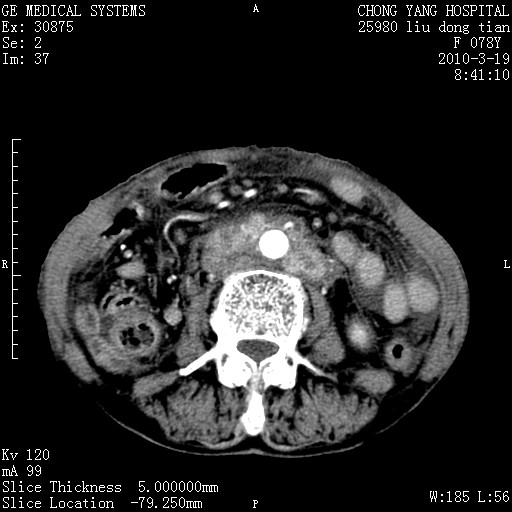

标题: CT25199:F 78Y 腹胀半年 消瘦乏力 [打印本页]

胆囊壁增厚并明显强化,胆囊癌伴多发转移瘤可能性大,淋巴瘤不除外,右肾囊肿,胸腹水.

考虑nhl,肝、脾、腹膜腔及腹膜后多发淋巴结受侵,腹水,右肾囊肿,慢性胆囊炎,右侧少量胸腔积液。

胰头有肿块形成,胰头ca伴肝脾、腹膜腹膜后转移

胆囊有软组织影有强化,支持胆囊癌,肝脾、腹膜后淋巴结转移。

nhl的淋巴结多围绕主动脉,而且主动脉会移位,所以不考虑nhl。

分开来讲:肝左叶、尾叶病灶有不均强化像肝癌;

脾脏病灶无强化,像多发囊肿或淋巴管瘤,不除外淋巴瘤(低强化);

胆囊增生性病变:胆囊癌,腺肌增生症,慢性胆囊炎;

肝门、胰腺头、腹膜后多个团块: 淋巴瘤,转移;

腔静脉肝内段细小有无布加可能?

一元论最好了 淋巴瘤所致改变; 胆囊癌转移不像,胆囊周围肝组织清晰,肝癌淋巴结转移?三元论都不止。

胰头ca伴肝脾、腹膜腹膜后转移!

最后报的胰头癌多发转移,脾脏单独考虑囊肿或淋巴管瘤。